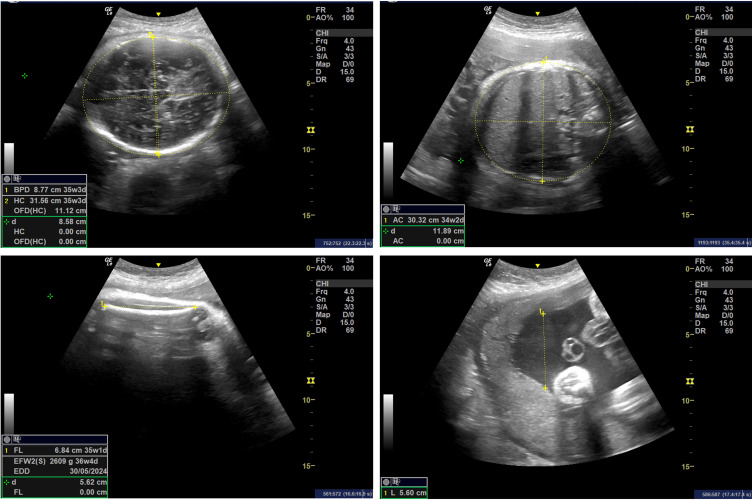

Case illustration: An 18-year-old woman, G3P2A0, at full-term pregnancy, presented for elective cesarean section. The patient had no complaints and exhibited no signs of labor at the time of admission. Laboratory findings revealed anemia, with a hemoglobin level of 7.2 g/dL. She received two units of packed red cell (PRC) transfusions preoperatively. A cesarean section was performed, delivering a healthy baby boy weighing 2720 grams and measuring 47 cm. After a thorough discussion and informed consent regarding contraceptive options, the patient and her husband opted for Pomeroy sterilization, as they felt their family was complete.